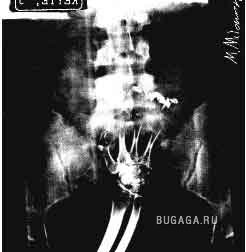

Ни для кого теперь уже не секрет, что у людей есть жопы. У каждого она своя и у всех разные. Жопы бывают человеческие и другие, большие и маленькие, плоские и выпуклые, висячие и упругие, в общем, всякие. А еще жопы бывают сытые и голодные. У кого сытая попа, тот её холит и лелеет, она вся такая ранимая и нежная. А у кого голодная жопа, тот её пичкает всем, что попадётся под руку, может затолкать туда всё, что угодно. Такую жопу ничто не берёт. Ни слово, ни дело, ни заноза, ни пуля, ни штык, ни добрый подсрачник! Прозвали их люди чудо-жопы! Чудо-жопы имеет не каждый, а только тот, кто регулярно упражняется в скармливании жопе различных инородных предметов. Этих ректальных сластолюбцев люди тоже кое-как прозвали, но мы не будем отвлекаться, с нас достаточно знать факт, что люди имеют жопы. Кто воспламенел желанием поэкспериментировать, но не знает, что именно засунуть в недра своего драгоценного проголодавшегося зверя, предлагаю посмотреть варианты. Ну а кому просто интересно, тот глазеет на серию снимков, сделанных медиками в разное время и в разных странах, но в одинаково патологичных случаях. Можно также прочитать пару случаев кормления, и чем это закончилось. Кого картинки могут задеть за живое, не принимайте близко к… живому :):):)

Список вещей, извлеченных из чудо-жоп:)

Разные предметы:

Вибраторы -23

Фалоимитаторы -15